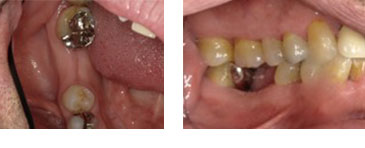

右下6番 フラップレス埋入(成熟側埋入)

BEFORE

AFTER

| 金額 | ¥420,000(税抜) |

| 期間 | 約2ヶ月半 |

| リスク | オペから6週までは過大な力がかかると骨の2次安定が得られないことがあるため、注意を要する。 |